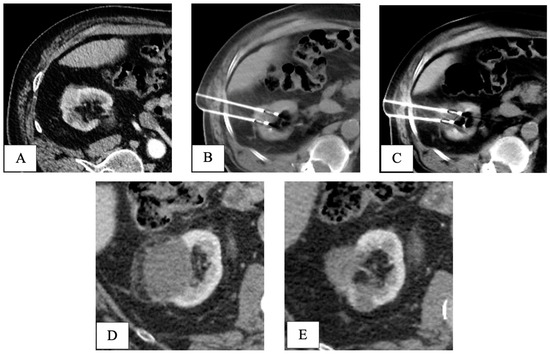

Final pathology following RPN revealed five pT1 papillary-type renal cell carcinomas and one fibrotic nodule without any sign of cancer. At a mean follow-up of 40.5 months, all patients in both groups were alive without signs of recurrence (Table 2). An example of the oncologic efficacy of CT-guided cryoablation is showed in Figure 4.

Figure 4.

CT-guided cryoablation of de novo kidney tumor in a patient who underwent liver transplant 5 years before for HCV-related HCC. Legend: (A) preliminary contrast-enhanced CT scan confirmed the presence of a T1a DKT sizing 2cm in the right kidney; (B) under CT guidance, 2 cryoprobes were placed within the renal lesion; (C) control CT scan showed the presence of a hypodense ice-ball, including all the volume of the nodule to be treated. (D) One-month follow-up CT scan detected complete response, with a hypodense cryo-induced ablation area; (E) 3-year follow-up CT scan demonstrated prolonged response, with ablation area decreasing in size. DKT, de novo kidney tumor.